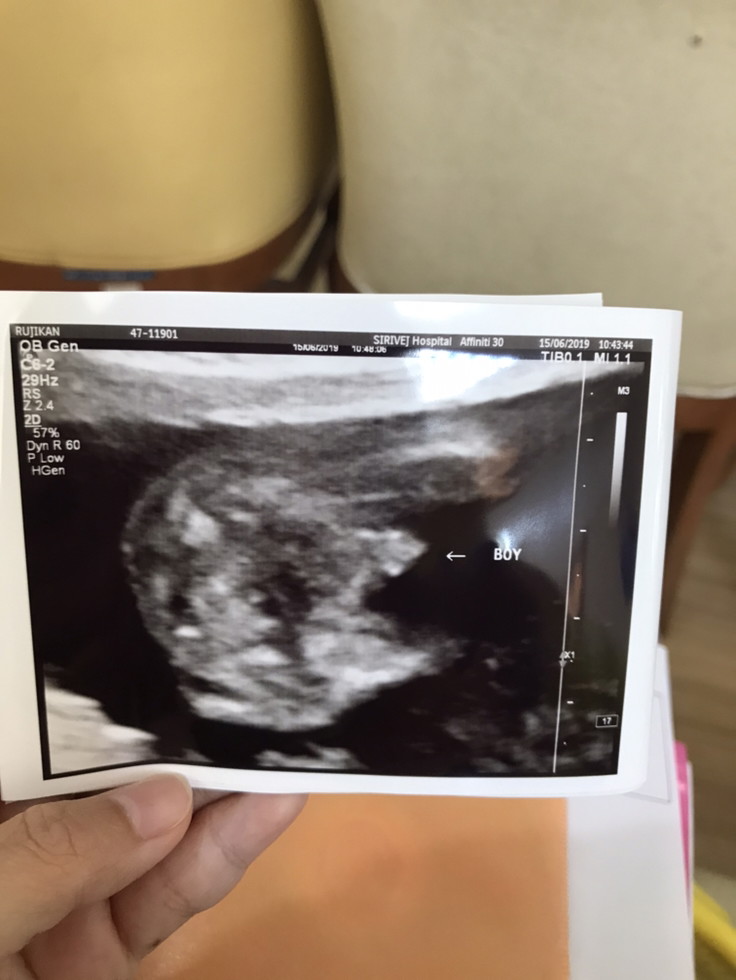

เจอตอน12สัปดาห์ค่ะ ชายชัดเจน